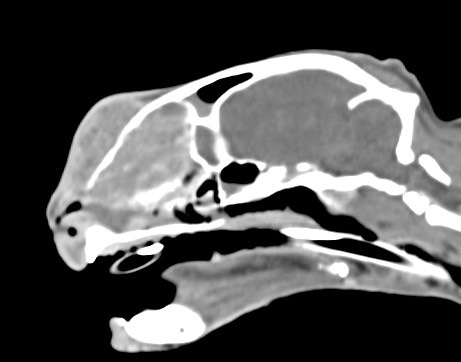

狗狗 鼻腔腫瘤 惡性上皮癌

鼻腔腫瘤的診斷需要仰賴電腦斷層掃瞄定位病灶處,同時使用鼻腔內視鏡探查、採樣才能確診,同時有這兩項設備的醫院並不多,所以臨床上並不是那麼容易確診。狗狗的慢性鼻炎維持3-4個月,越來越嚴重,他院轉診至築心,經由內視鏡+電腦斷層確認為鼻腔上皮癌,而且由於病程時間長,已經轉移至胸腔,代表壽命不長了,至少家人心中有個答案,有心理準備陪狗狗最後一段路。

狗狗 鼻腔腫瘤 淋巴癌

鼻腔腫瘤的診斷需要仰賴電腦斷層掃瞄定位病灶處,同時使用鼻腔內視鏡探查、採樣才能確診,同時有這兩項設備的醫院並不多,所以臨床事並不是那麼容易確診。狗狗如果有打噴嚏、鼻分泌物 鼻塞,對藥物治療反應不好, 就還是要做進一步檢查才會比較安心唷!